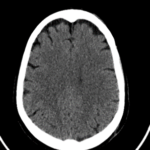

Las calcificaciones del sistema ventricular constituyen un error clásico y se confunden con hemorragias o masas.

Fig. 3.

Dentro de las astas posteriores de los ventrículos laterales a veces nos encontramos con xantogranulomas de los plexos coroideos. Debemos tener presente que estos se componen por quistes neuroepiteliales sin valor patológico.

Cavidades del septum. El septum es un fino tabique formado por dos láminas gliales ubicadas entre el cuerpo calloso en dirección cefálica y el trígono caudalmente. Existen tres variantes: el cavum pellucidum, cavum vergae y cavum interpositum.

Fig. 4.